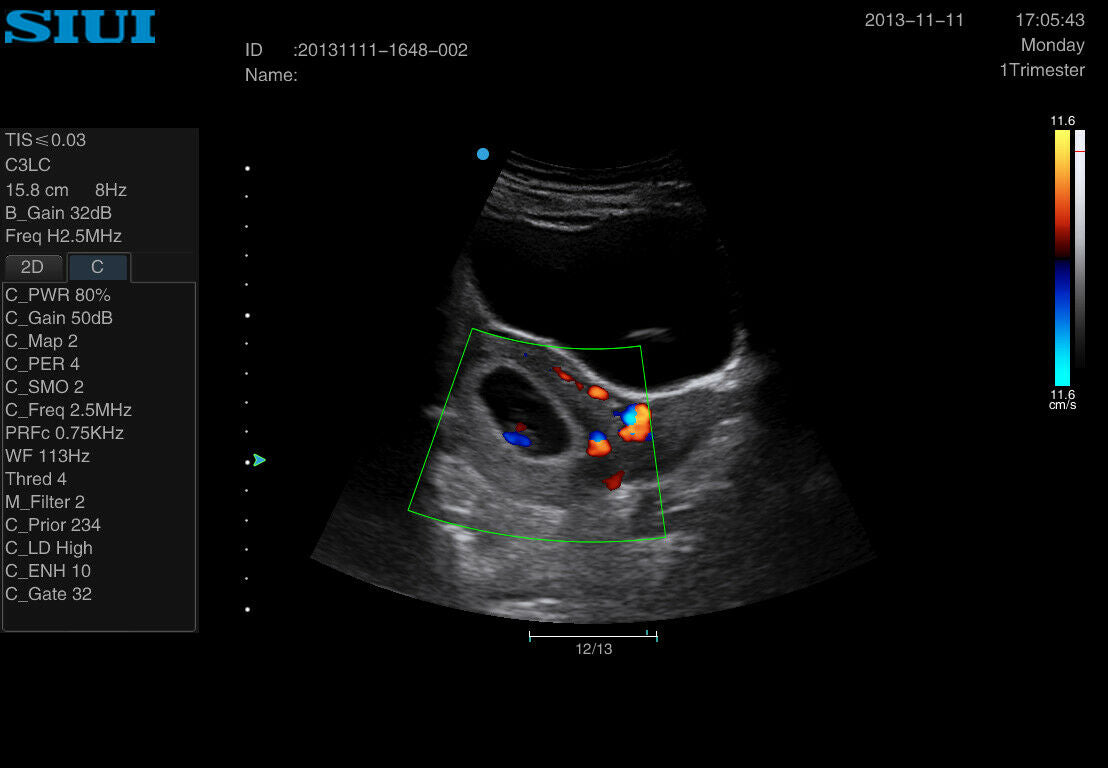

Portable OB/GYN Ultrasound Machine: SIUI Apogee 2300

The Portable OB/GYN Ultrasound Machine, specifically the SIUI Apogee 2300, represents a breakthrough in medical imaging technology. Designed with convenience in mind and equipped with advanced features, this ultrasound machine is an excellent choice for obstetrics and gynecology practitioners who need reliable, high-quality imaging on the go.

This state-of-the-art machine comes with two probes, ensuring versatility for different diagnostic needs. The SIUI Apogee 2300 supports DICOM (Digital Imaging and Communications in Medicine) which allows seamless integration with hospital information systems and ensures efficient workflow and storage management. The portability of this machine does not compromise its performance, as it delivers crystal-clear images that are critical for precise diagnostics.

Another key advantage is the high resolution imaging capabilities. The portable OB/GYN ultrasound machine, with its advanced image processing software, delivers detailed images that can be crucial for diagnosing various conditions. From routine prenatal scans to complex gynecological assessments, the SIUI Apogee 2300 stands out in its ability to provide accurate and reliable results.

Furthermore, the inclusion of DICOM compatibility enhances the overall functionality of the SIUI Apogee 2300. With this feature, images and patient data can be easily shared and accessed across different platforms, promoting collaborative care and ensuring that patient records are comprehensive and up to date. This interoperability is crucial in modern medical practice, where integration and communication across systems are key to efficient patient management.

In summary, the Portable OB/GYN Ultrasound Machine SIUI Apogee 2300 with 2 Probes and DICOM support is a powerful, versatile, and efficient tool for modern obstetrics and gynecology practices. It provides high-quality imaging, user-friendly operation, and robust durability, all while ensuring patient comfort and efficient data management. Whether for routine check-ups or complex diagnostic procedures, this ultrasound machine is an invaluable addition to any healthcare setting, offering both clinicians and patients numerous benefits.